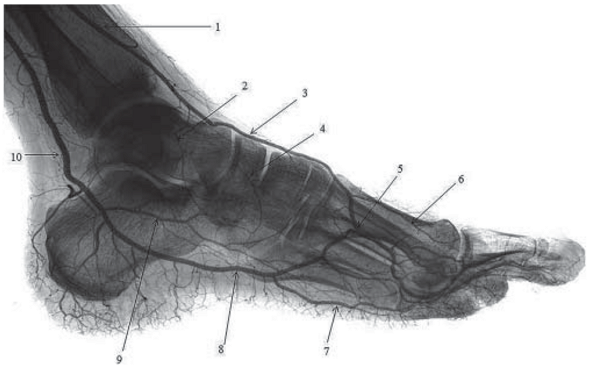

При боковой укладке ТАС проецируется на тыльную поверхность костей предплюсны в проекции мягких тканей, затем наслаивается на основание I плюсневой кости и область первого межпальцевого промежутка, где отдает крупную подошвенную ветвь. Последняя анастомозирует с латеральной подошвенной артерией, формируя вертикально ориентированную дугу в дистальном отделе стопы. В области середины таранной и ладьевидной костей от ТАС отходят соответственно латеральная предплюсневая и дугообразная артерии, которые направляются латерально и вниз. На уровне середины тела плюсневых костей от ТАС берут начало тыльные плюсневые артерии. Они следуют параллельно плюсневым костям, а в области их головок делятся на тыльные пальцевые артерии (рис. 1).

Рис. 1. Артерии стопы. Поствитальная ангиограмма. Боковая проекция: 1 – передняя большеберцовая артерия; 2, 4 – латеральная предплюсневая артерия; 3 – тыльная артерия стопы; 5 – глубокая подошвенная ветвь; 6 – тыльная плюсневая артерия; 7 – подошвенная плюсневая артерия; 8 – латеральная подошвенная артерия; 9 – медиальная подошвенная артерия; 10 – задняя большеберцовая артерия